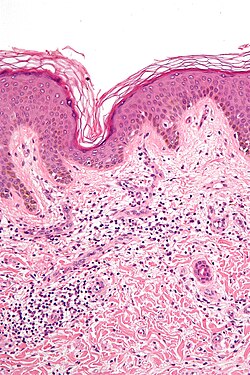

Microscopic

- Loss of basal cells (stratum basale) -- key feature.

- Loss of rete ridges/formation of pointed rete ridges "sawtoothing".

- Interface dermatitis (lymphocytes at dermal-epidermal junction).

- Hypergranulosis; stratum granulosum thickened (grossly seen as "Wickham stria" = white lines).

- Hyperkeratosis; stratum corneum thickened.

- Necrotic basal cell in dermis = colloid bodies = Civatte bodies.[16]

- Pink bodies approximately the size of a keratinocyte.